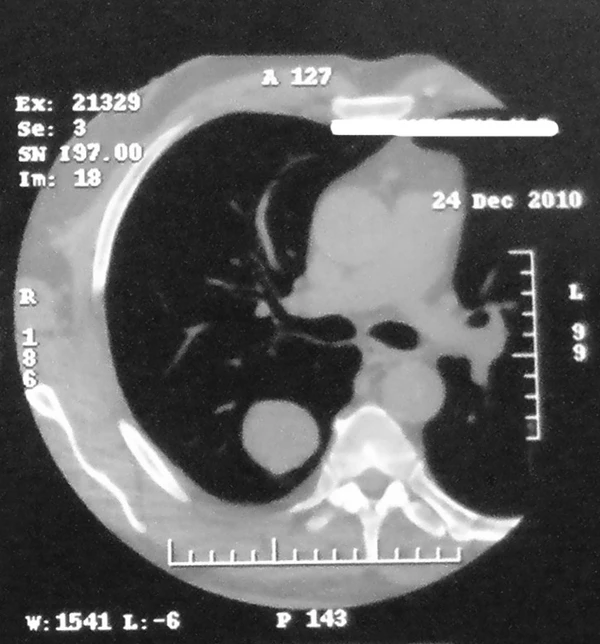

Основным преимуществом компьютерной томографии перед обзорной рентгенографией органов грудной клетки в обследовании пациентов с гамартомой лёгкого является возможность более детальной оценки внутренней архитектуры опухоли благодаря получению тонких срезов. В связи с этим включения кальция и жира лучше визуализируются при компьютерной томографии, чем при рентгенографии[2][10].

При компьютерной томографии органов грудной клетки гамартомы всех гистологических разновидностей дифференцируются в виде объёмного образования овальной формы с чёткими контурами различного диаметра, располагающегося на фоне неизменённой лёгочной ткани без реакции близлежащей междолевой или костальной плевры. Примерно в половине случаев структура гамартомы является неоднородной: либо за счёт центрально расположенных участков обызвествления (в 15—30 %), либо за счёт участков пониженной до −130 HU плотности (жировая ткань, в 34—50 %). Сочетание включений жира и кальция в одной опухоли является характерным признаком гамартомы. Частота обызвествления возрастает с увеличением размеров гамартомы: от 10 % для опухолей менее 2 см до 75 % для гамартом более 5 см[2]. При расположении опухоли в плащевой части лёгкого она имеет подчеркнутые контуры и гладкую поверхность, а при локализации гамартомы в толще лёгочной ткани её удалённый от корня полюс имеет подчёркнутые контуры и гладкую поверхность, обращённый же к корню лёгкого полюс остаётся чётким, но приобретает волнистый характер за счет множества коротких фиброзных тяжей, распространяющихся в ткань лёгкого. Отмечается также характерная ориентация длинной оси гамартомы: при расположении этой опухоли в любом отделе лёгочной ткани её длинная ось всегда направляется в сторону корня лёгкого[3].

При компьютерной томографии с болюсным контрастным усилением изображения отмечается постепенное повышение плотности гамартомы на протяжении всех фаз контрастирования. Характерно, что в артериальную фазу увеличение плотности ткани образования происходит на 57,2 %, в венозную фазу — на 26,4 %[Комм 1][3].